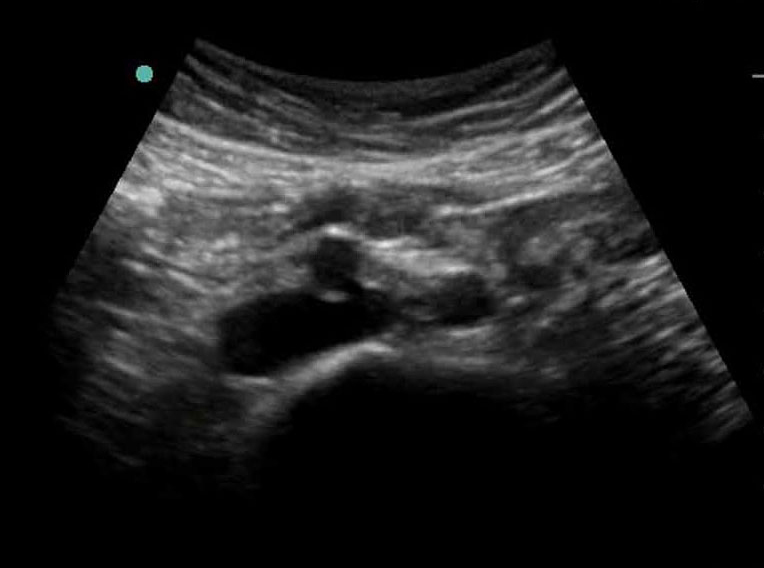

Bild: Aorta, distale Verzweigung, transversal